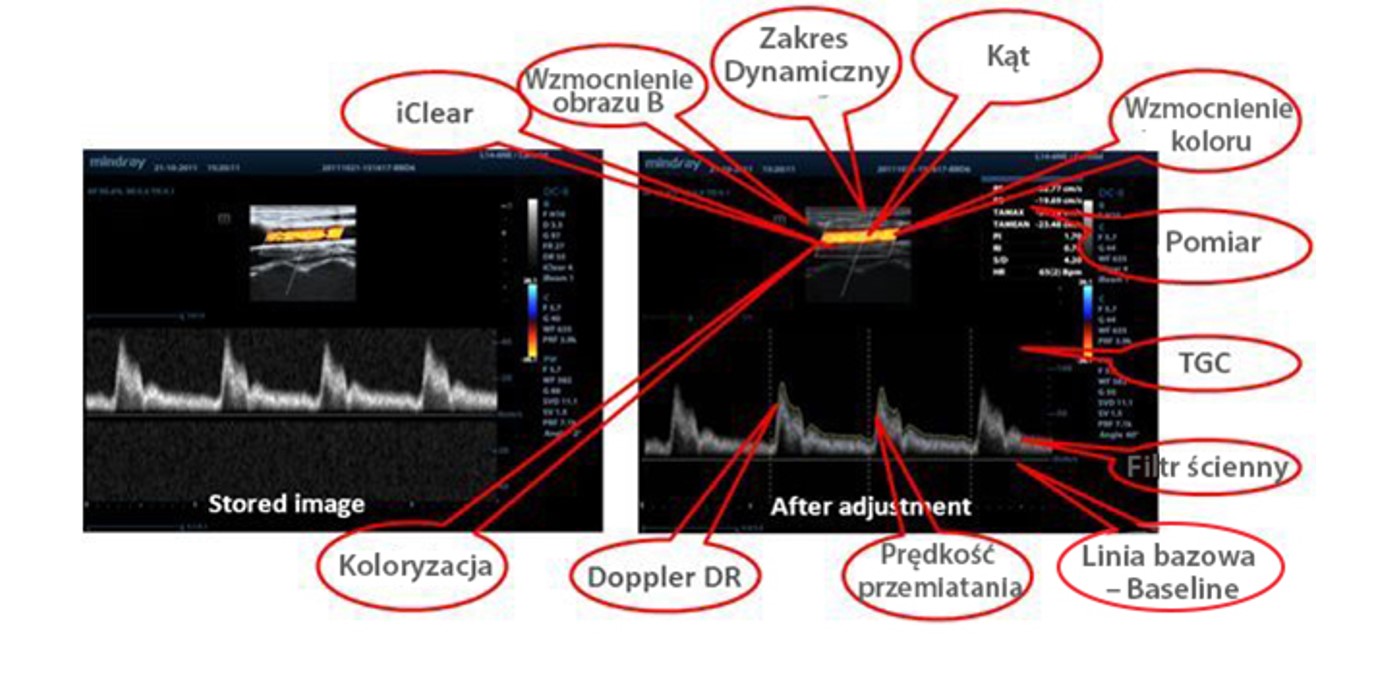

Raw Data

Umo?liwia optymaln? elastyczno?? w zakresie przetwarzania zgromadzonych obraz├│w, w tym dostosowywania parametr├│w, dodawania komentarzy i pomiar├│w, co zapewnia maksymaln? wydajno?? podczas skanowania.